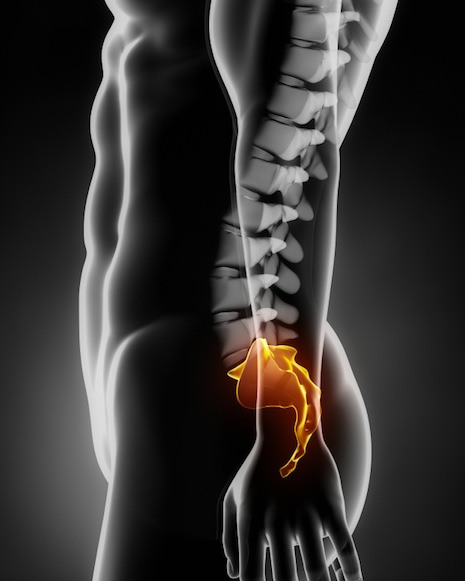

Είκοσι μόλις λεπτά διήρκησε η πρώτη ενδοσκοπική θεραπεία της κύστης κόκκυγος στην Ελλάδα, σε 32χρονο ασθενή, η οποία πραγματοποιήθηκε την περασμένη εβδομάδα και στέφθηκε με απόλυτη επιτυχία! Η επέμβαση ήταν ανώδυνη, αναίμακτη, πραγματοποιήθηκε με τοπική αναισθησία και ο ασθενής λίγες ώρες αργότερα επέστρεψε στην οικία του!